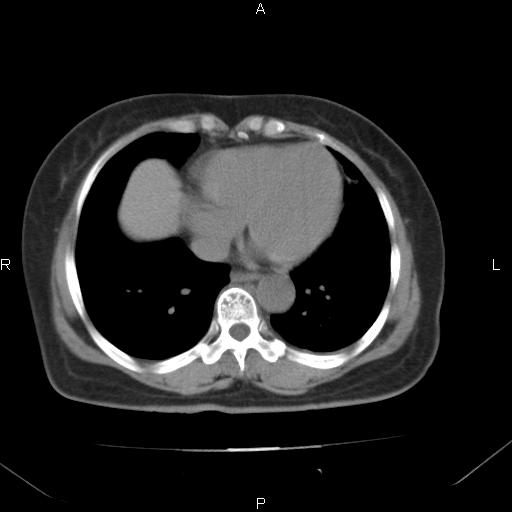

胸腺瘤

女、63Y 双眼睑下垂,早轻晚重。 胸腺瘤???

结果胸腺瘤